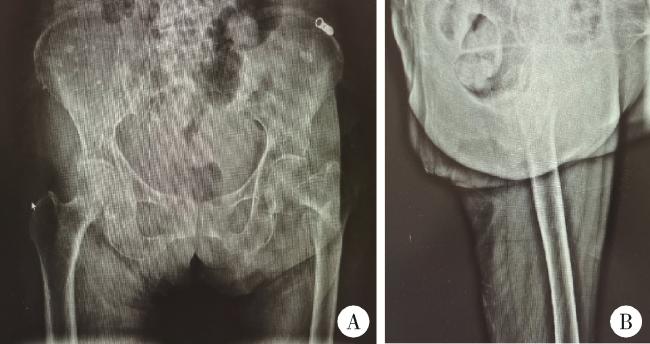

图2 患者股骨粗隆间骨折闭合复位内固定术术中透视X线片

Figure 2 X-ray in closed reduction and internal fixation of femur intertrochanteric fracture of paitient

A, following closed reduction, the X-ray of the left hip confirmed a well-reduced fracture; B, after inserting the guide pin into the femoral medullary cavity, reaming was performed; C, subsequently, the proximal femoral intramedullary nail and lag screw were inserted, and an X-ray of the femur was taken.

老年女性患者,88岁,患者2020年10月26日步行时不慎摔倒,左髋着地。于北京大学第一医院急诊查双髋X线片示左侧股骨粗隆间不稳定骨折(图 1)。查体:生命体征平稳。左髋强迫外展外旋位,左下肢短缩约2 cm。左髋局部压痛,轴向叩击痛,活动度拒查。双下肢感觉无异常,双侧足背动脉搏动可。入院后行左股骨粗隆间骨折闭合复位InterTAN髓内钉固定术,术中复位满意,过程顺利(图 2),术后复查髋关节X线片示骨折复位及内固定物位置满意(图 3)。术后次日开始骨化三醇、碳酸钙D3抗骨质疏松治疗,术后1周加用地舒单抗。术后1个半月部分负重,术后3个月可下地行走,无明显不适。2021年10月7日(术后12个月)无明显诱因出现左髋疼痛,进行性加重,逐渐出现行走困难。2022年2月28日(术后16个月)于北京大学第一医院门诊复查双髋正位X线片考虑左侧股骨颈骨折,内固定物对髋臼侧骨质有一定破坏(图 4),为行治疗收治入院。既往有高血压、腔隙性脑梗、房颤病史。查体:生命体征平稳,左髋关节周围压痛明显,无红肿,关节活动受限,疼痛明显,查体配合差。入院查血常规:白细胞计数7.1×109/L,中性粒细胞计数6.5×109/L,中性粒细胞百分比92.3%,超敏C反应蛋白4.27 mg/L,降钙素原0.02 μg/L,除外感染后行左髋关节内固定物取出加半髋关节置换术,术中未见浑浊关节液及组织液,既往股骨粗隆间骨折部位已完全愈合,新发股骨颈骨折(图 5),髋臼外上方有一处头颈螺钉切割出的缺损区,直径约1.5 cm,内有纤维瘢痕组织填充,取局部组织留取病理,送咽拭子细菌培养,培养结果阴性。术中采用骨水泥型11号股骨假体柄(长度200 mm)和外径44 mm的双极金属股骨头行半髋关节置换术,术后复查髋关节X线片(图 6),可见髋臼侧骨质密度减低。术后预防性抗感染治疗,术后1周出院,院外继续抗骨质疏松治疗。术后3个月患者反馈左髋疼痛及功能明显改善,患者及家属对治疗满意。